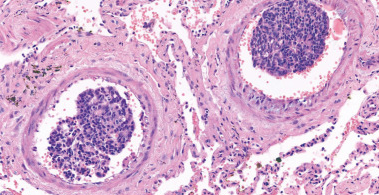

Ινοβλαστική πολλαπλασίαση αγγειακού έσω χιτώνα, θρόμβωση, εμβολισμός από καρκινικά κύτταρα (Ευγενική παραχώρηση Dr. V. Penopoulos)